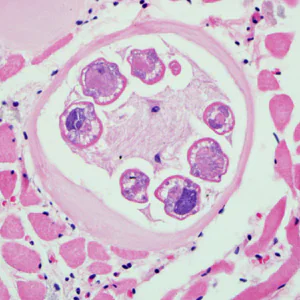

Encysted larvae of Trichinella in tissue, stained with hematoxylin and eosin (H&E).